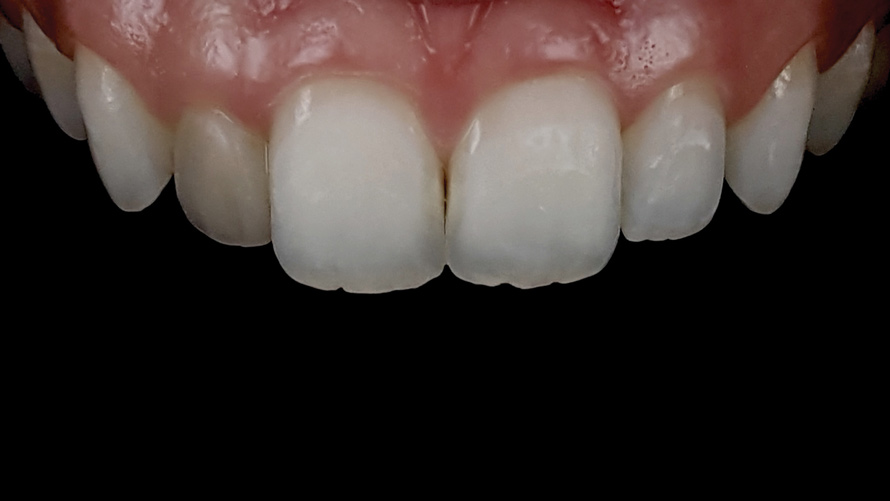

(18. and 19.) Tooth shade analysis of value, chroma, and hue taken with a smartphone and an EALS device.

Figure 18

Figure 19

Shade Selection and Laboratory Communication

The most utilized intraoral photographs in the field of dentistry are perhaps those that capture shade information (Figure 18 and Figure 19). The analysis of color (ie, value, chroma, hue) in dentistry is a critical step in the fabrication of esthetic indirect restorations, such as all-ceramic crowns and porcelain laminate veneers. The ability to properly communicate this information with the dental laboratory is essential to ensure an appropriate shade match, a reduction in chairtime and overhead, and most importantly, a satisfactory patient experience and treatment outcome. In recent years, the use of polarized light photography as an aid in the shade selection process has become extremely popular. For some EALS devices, special polarizing filters have been specifically designed to fit over the light-emitting portion of the device (Figure 20 and Figure 21). The images produced using polarized light photography demonstrate an elimination or reduction in the specular reflection of hard and soft tissue, resulting in a matte-finish appearance of the dentition and gingiva. These types of photographs aid the ceramist in identifying areas of opacity and translucency, crack lines, hypo- or hypercalcification, and other internal features of the dentition that may not be readily visible without such a filter (Figure 22).